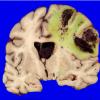

Hemorrhage, hypertensive (5)